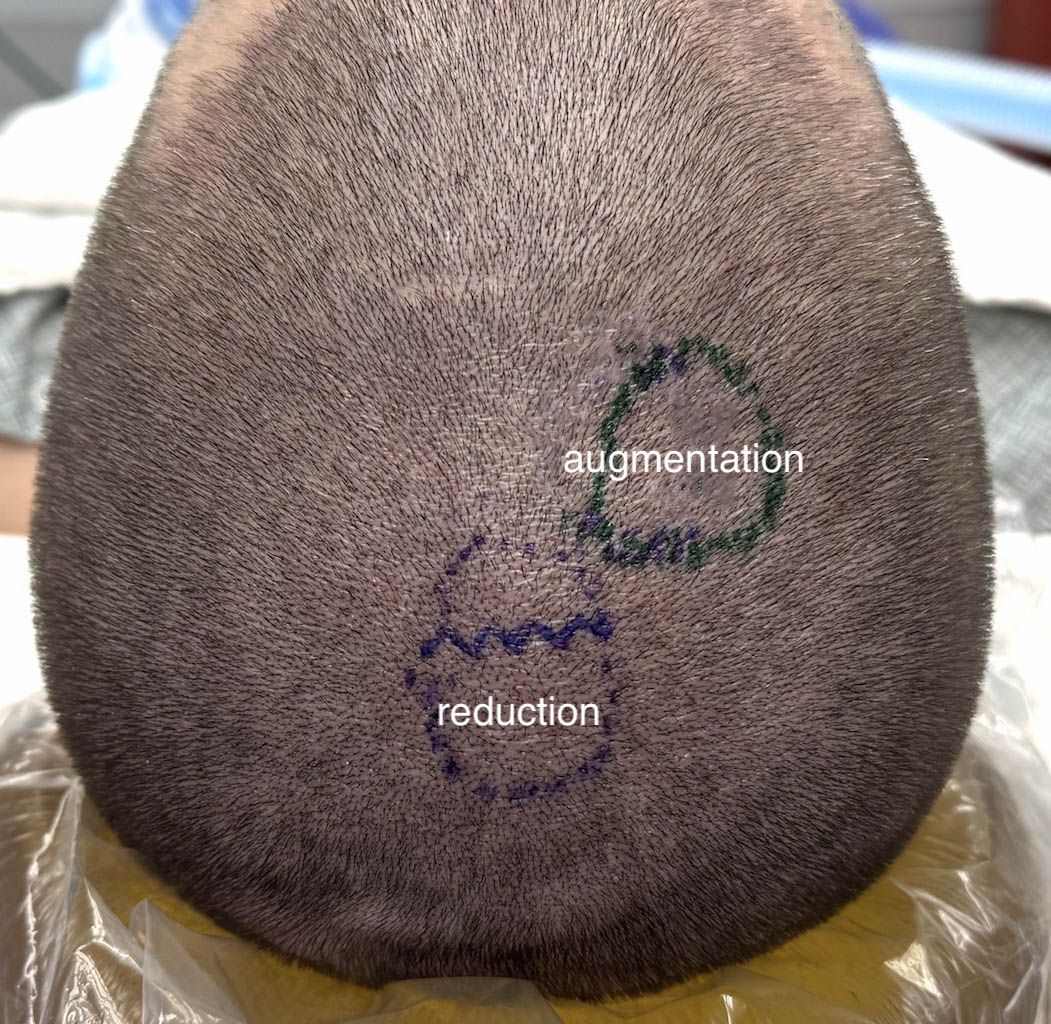

Desire for head reshaping for a high sagittal ridge and low parasagittal-upper parietal skull regions.

Skull reshaping with a combination of sagittal crest reduction and a custom parasagittal-parietal skull implant.

Desire for head reshaping for a high sagittal ridge and low parasagittal-upper parietal skull regions.

Skull reshaping with a combination of sagittal crest reduction and a custom parasagittal-parietal skull implant.